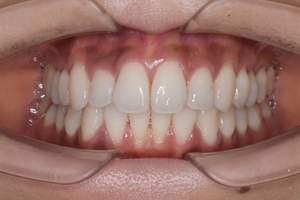

歯石除去

治療前

治療後

| 年齢 | 40歳・男性 |

| 主訴 | 歯石をとりたい |

| 治療内容 | 歯石除去 |

| 治療期間 | 30分 |

| 費用 | 約2,000円 |

| リスク・副作用 | ・歯ぐきの炎症が強いと歯石を取る際に出血することがあります。 ・処置後に歯がしみることがあります。 ・歯と歯の間に隙間ができるので、息が漏れ発音しにくいと感じることがあります。 ・歯ぐきの炎症が軽減すると歯ぐきが引き締まり、歯が長く見えることがあります。 |